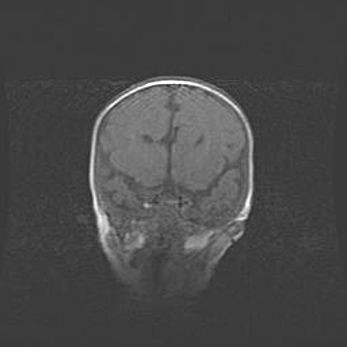

Множественные кисты обоих полушарий головного мозга, наибольшая из них в правой затылочной области. Ассиметричная атрофическая гидроцефалия.

Возраст: 7 месяцев

Вес: 5660 г

Пол: мужской

Окружность головы: 41,5 см

Срок гестации: 28-29 недель

Кисты головного мозга развиваются в результате многоочаговых некрозов вещества мозга и возникают вследствие перенесенной перинатальной инфекции, менингитов, энцефалитов, асфиксии, родовой травмы, расстройств мозгового кровообращения различного генеза. Образованию кист в веществе головного мозга плодов и новорожденных способствуют такие факторы, как высокое содержание в нем воды, недостаточная (или отсутствие) миелинизация и слабая астроглиальная реакция на повреждение.

Кисты могут сочетаться с гидроцефалией и другими поражениями головного мозга.